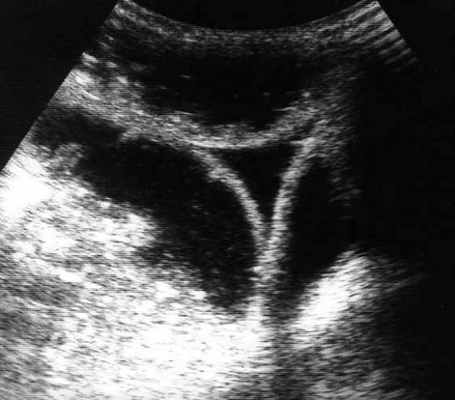

УЗД признаки тонкокишечной непроходимости

Основные УЗ-признаки при непроходмости- это визуализация расширенных петель тонкой кишки, сниженная перистальтика, свободная жидкость между петлями (танга) и в брюшной полости. Также УЗИ иногда позволяет обнаружить причину обструкции, например, опухоль, утолщение стенок терминального сегмента подвздошной кишки при болезни Крона и т.д. УЗИ может решить диагностическую дилемму при неоднозначных рентгенологических признаках на обзорной рентгенограмме брюшной полости. Лимит метода заключается в низкой специфичности при оценки состояния брыжейки, а также зависимость качества диагностики от конституции пациента и опыта оператора.

примеры сонограмм с расширенными петлями тонкой кишки

УЗИ позволяет прекрасно лоцировать свободную жидкость в брюшной полости